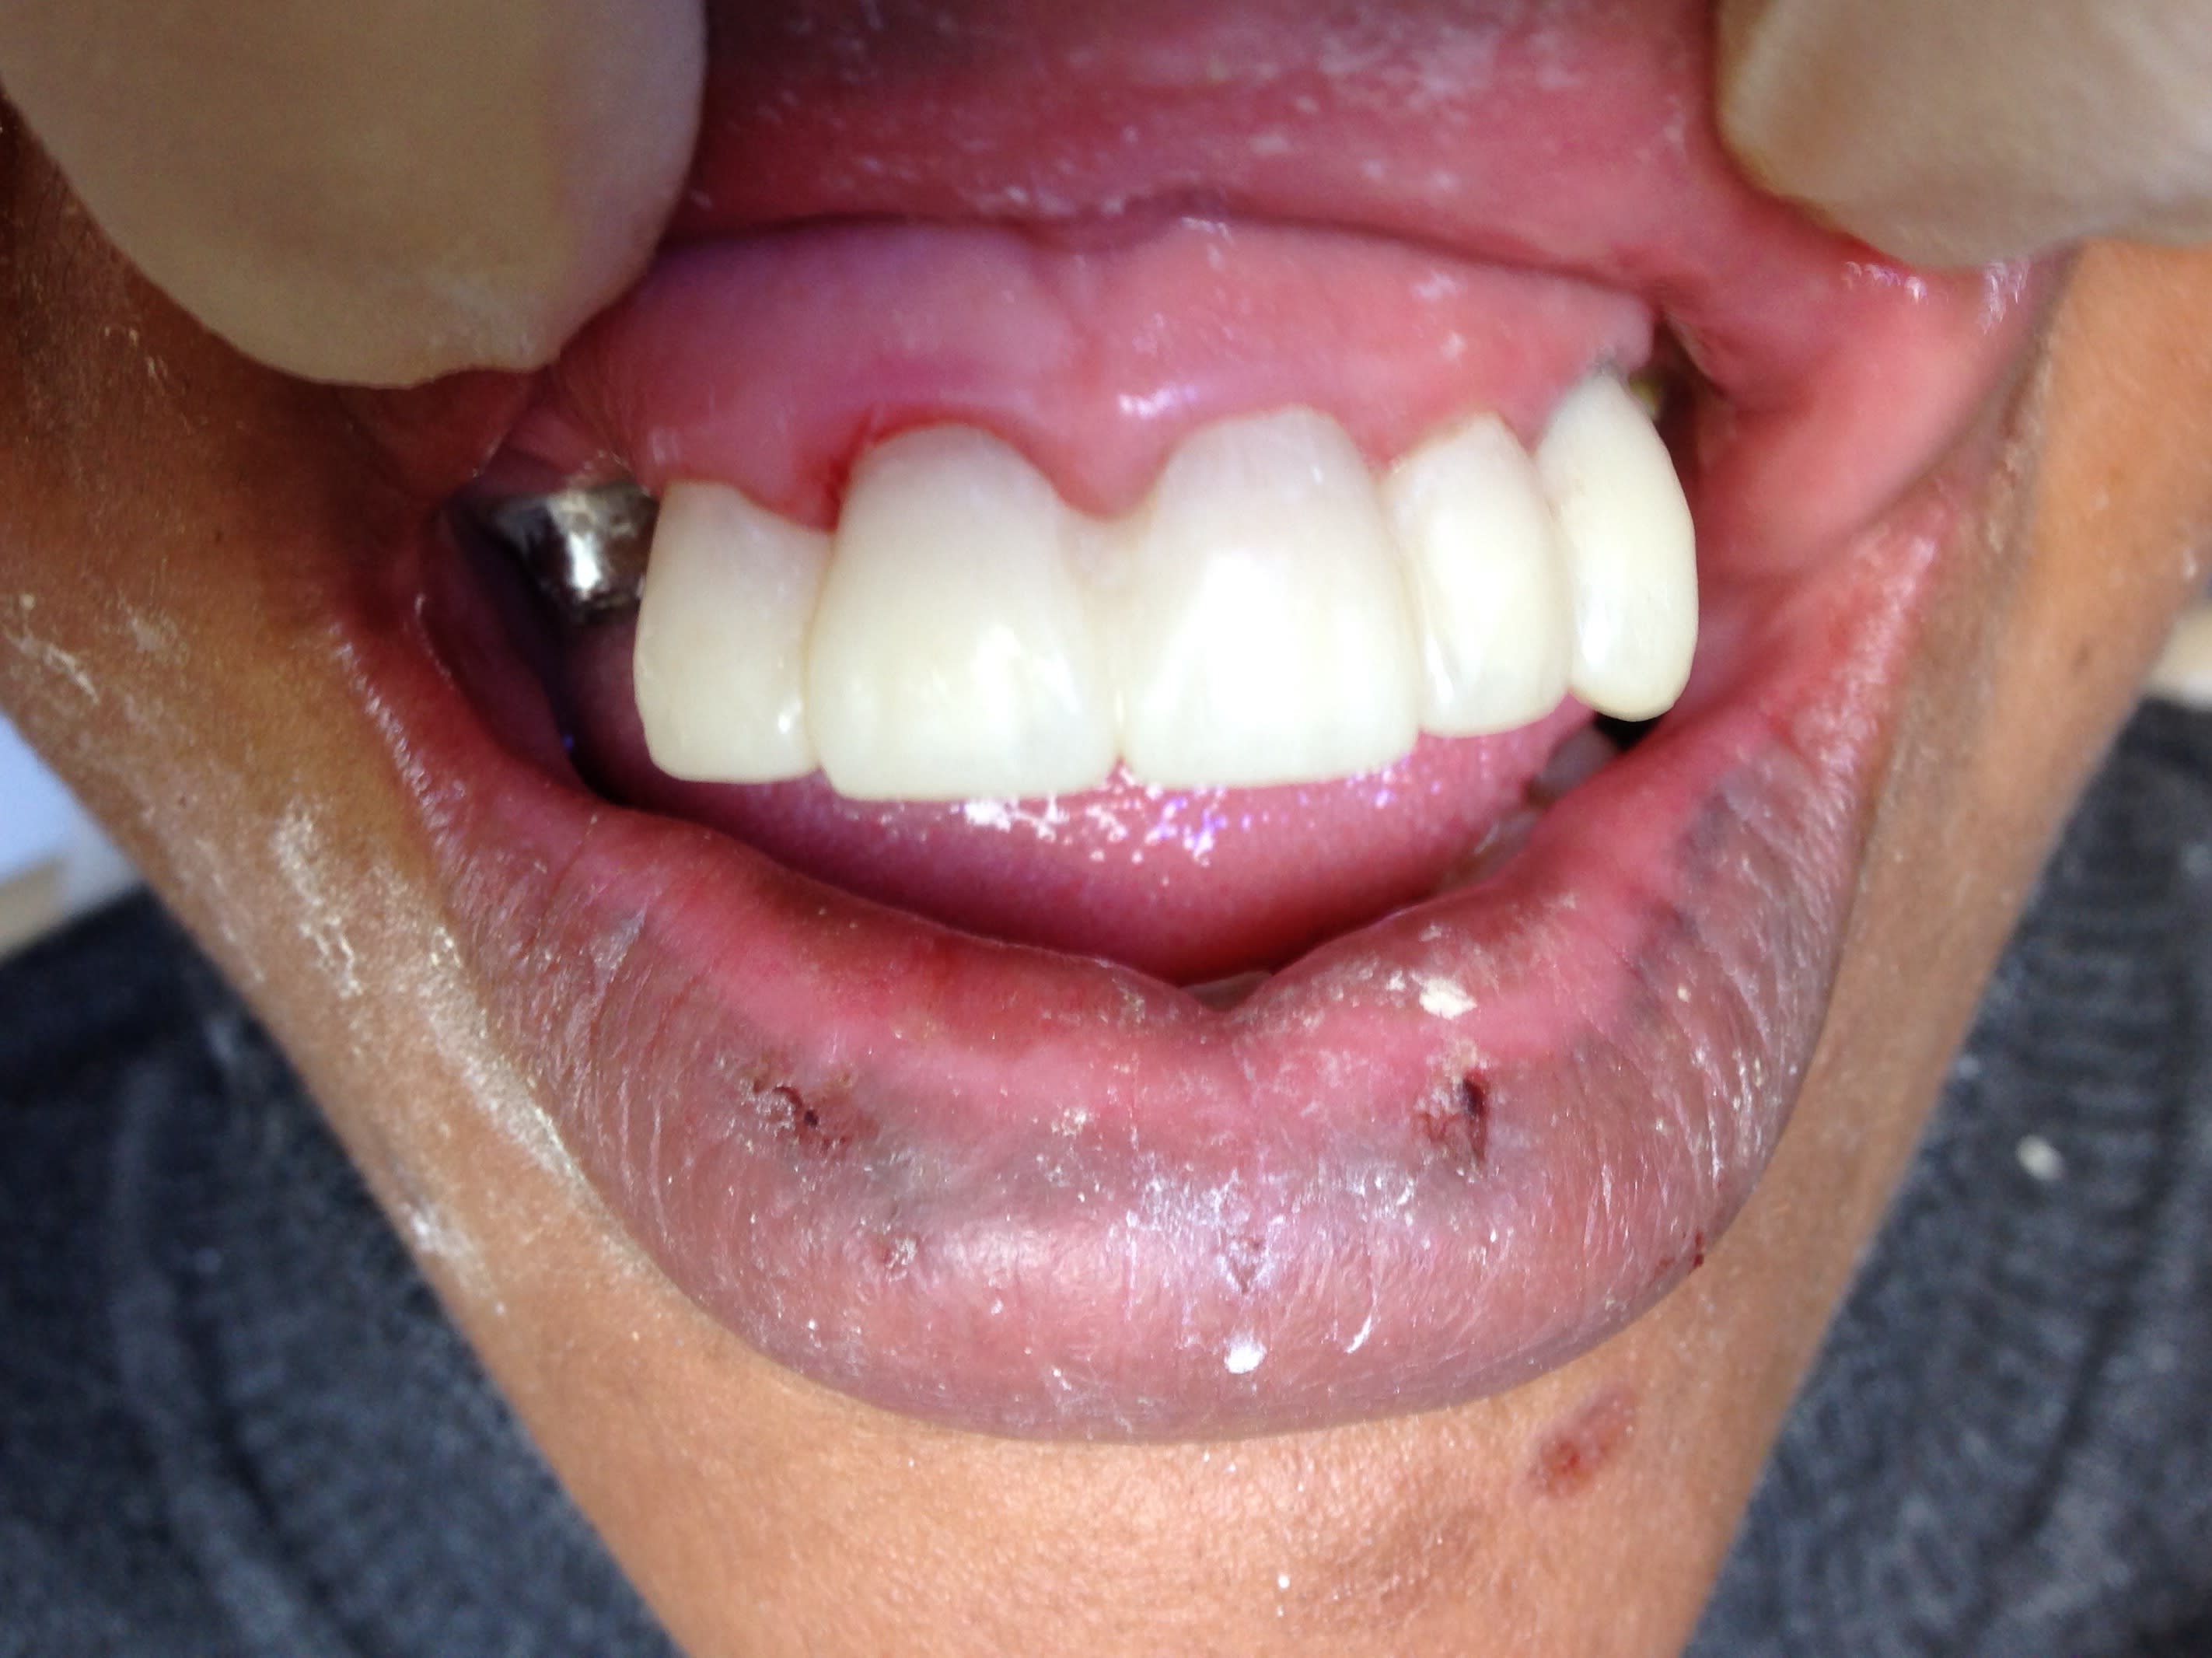

Enlaye regarde voir : les premières photos avant l'augmentation de DVO et les dernières après une augmentation de 2 mm . Je lui ai rabotée ses incisives provisoires . Ça te semble correct l'augmentation de DVO ? Faudra que je lui rabote en V sa canine . Mais bon je peux pas trop car tout le secteur antérieur est proversé.

Img 1293 pjgzyi - Eugenol

Img 1294 yfvgb6 - Eugenol

Img 1302 r9ltlj - Eugenol

Img 1301 hws07l - Eugenol

Img 1299 canyxp - Eugenol

Si l augmentation de DVO est bonne ?

C est difficile a dire .

Parce que normalement il aurait fallu la caler derriere pour pouvoir donner le jeux sur les dents de devant .elle ne sert qu a ca laugmentation de DVO .

Or là tu as comblé les faces palatines des incisives , pour augmenter la dvo .

Mais rien n est perdu , on va s en sortir :-):

Tu vois , quand elle ouvre et elle ferme ,les incisives du bas font un petit arc de cercle ,quand tu la regardes de profil .

Et bien , c est le meme arondi que tu vas faire sur les cingulums des prov du haut .

A ce moment , une fois que tu as fait ca ,ssi la bouche est ratatinée ,c est que la dvo etait bonne .

Sur ton prov , la canine est beaucoup trop epaisse en lingual .lorsque tu vas diminuer tu pourras meme avoir un recentrage mandibulaire .

Donc il te faudra peut etre , dans un deuxieme temps, re creuser les cingulums des incisives du haut .il vaut mieux trop d espace que pas assez .

non les provisoires paraissent épaisses car j'ai diminué leur hauteur. Faut effectivement que je diminue l'épaisseur. Mais là il n'y a aucun contact entre les incisives du bas Et Du haut. L'augmentation de DVO c'est uniquement avec ma cire en postérieur que je l'ai obtenue. Y a minimum 2 à 3 mm d'overjet ( voir 4mm) avec l'enregistrement en RC

Au départ jte rappelle que c'était ça les provisoires et j'ai eu droit à "elle va décapsuler les bières " hein ? 😊😊😊 Donc En diminuant leur hauteur elles paraissent très épaisses.